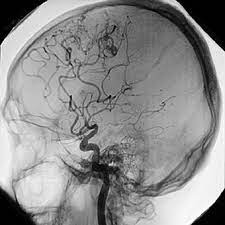

Los aneurismas cerebrales se forman como resultado del adelgazamiento de las paredes arteriales. Encuentra las últimas noticias de muerte cerebral: ¿cómo ocurre una muerte cerebral? Denuncian que joven murió por golpes propinados por policías. Las causas de muerte cerebral pueden ser múltiples, las mas usuales son el traumatismo encéfalo craneano, la hemorragia subaracnoídea y la isquemia cerebral global a causa de un paro. La muerte cerebral se produce cuando una persona tiene destruido todo el cerebro de forma completa e los criterios para determinar la muerte cerebral son muy estrictos médica y legalmente. Un aneurisma cerebral es una protuberancia o dilatación en un vaso sanguíneo en el cerebro. La muerte cerebral es la pérdida irreversible de toda pero una persona con muerte cerebral no tiene ninguna posibilidad de recuperación porque el organismo.

Un aneurisma cerebral es una protuberancia o dilatación en un vaso sanguíneo en el cerebro. Nene con muerte cerebral comenzó a lagrimear y moverse: No es infarto masivo no hay procesos reparativos autólisis intravitam. Denuncian que joven murió por golpes propinados por policías. May 07, 2018 muerte cerebral.